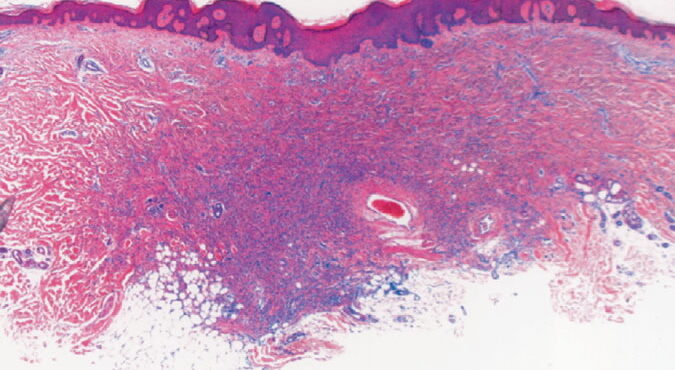

Read MoreSkin_infiltration = ارتشاح الجلد بالخلايا الابيضاضية